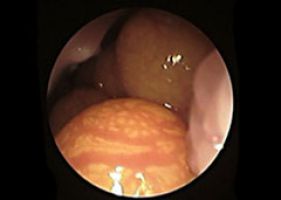

Die Endoskopie hat sich in den letzten Jahren zu einem der wichtigsten Verfahren in der Vogel- und Reptilienmedizin entwickelt. Sie bietet gerade bei Exoten vielfältige Einsatzmöglichkeiten wie Geschlechtsbestimmung, Chirurgie, Diagnostik und die Entnahmen von Probenmaterial -sogenannten Biopsien- zur weiteren Untersuchung innerer Organe.

Follikel auf dem Eierstock eines weiblichen Jemenchamäleons